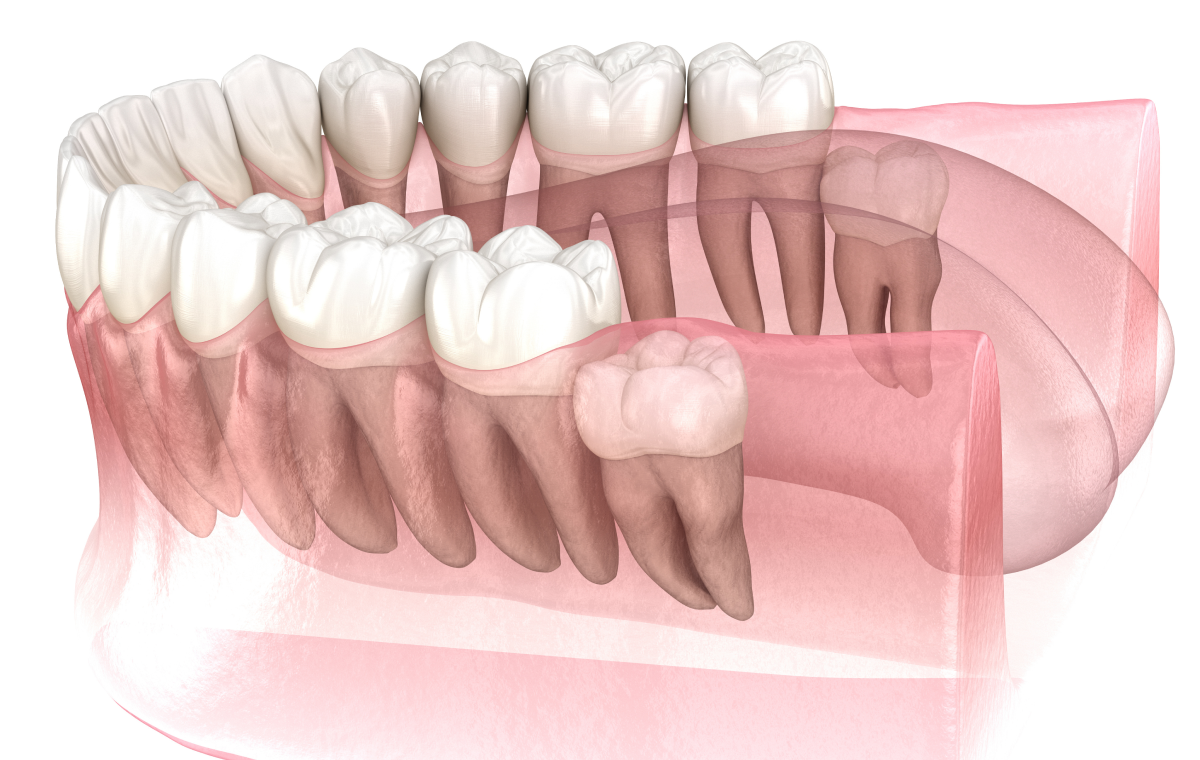

Chez de nombreux patients, les mâchoires ne disposent pas d’un espace suffisant pour accueillir correctement les dents de sagesse. Cette situation peut entraîner une éruption partielle ou une position anormale de la dent.

Lorsque la dent ne sort pas complètement, une partie reste sous la gencive, favorisant l’accumulation de bactéries et de débris alimentaires.

Impact sur les dents voisines

Une dent de sagesse mal positionnée peut exercer une pression sur la molaire adjacente. Cette situation favorise parfois l’apparition de caries sur la dent voisine, en raison d’un accès difficile au brossage. De plus, des résorptions osseuses ou dentaires peuvent survenir dans certains cas.

Chez les adolescents et les jeunes adultes, l’extraction des dents de sagesse est parfois envisagée à titre préventif. Lorsque les examens montrent un risque élevé de complications futures, l’intervention peut être proposée avant l’apparition de symptômes.

Cette anticipation permet souvent une récupération plus rapide, car les racines sont encore en cours de formation et l’os plus souple.